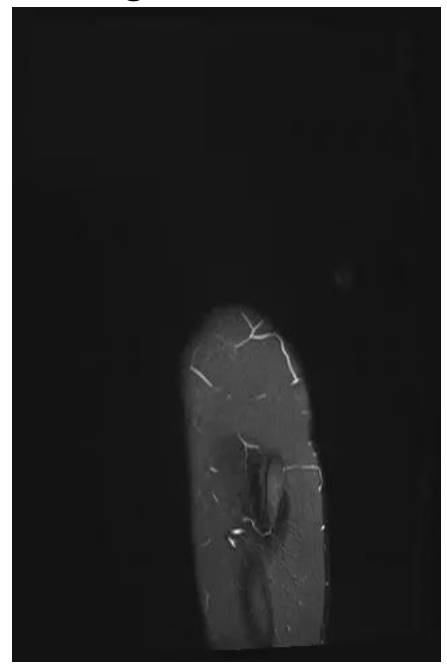

Before surgery: The MRI shows tumor tissue infiltrating the soft tissue, starting from the 4th lumbar vertebra and extending through the sacrum and iliac crest to the hip joint, causing bone destruction.

Post-surgery: The X-ray shows the reconstruction procedure after resection.